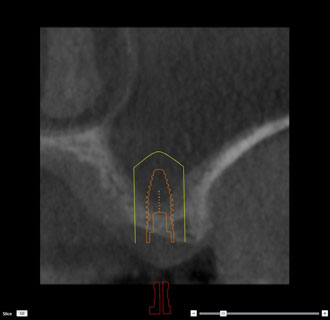

インプラント シュミレーション画像2

インプラント治療や、埋もれている歯の抜歯、口腔内の手術などを行う場合には、まずコンピューターでシミュレーションを行います。

CT画像をノーベルクリニシャン®︎で処理することで、様々な角度から画像を分析することが可能です。ノーベルクリニシャン®︎を使用する事で、より安全な治療が可能となりました。